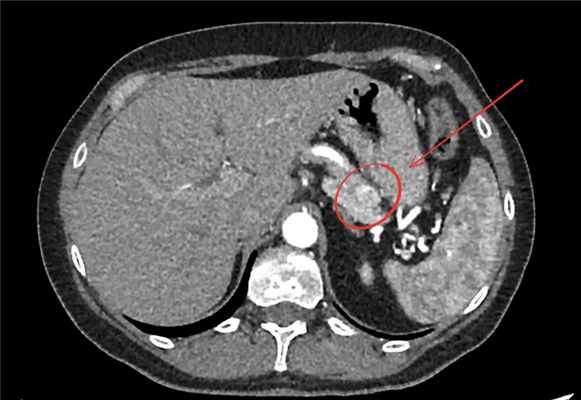

Рис.1 Инсулинома на компьютерной томографии